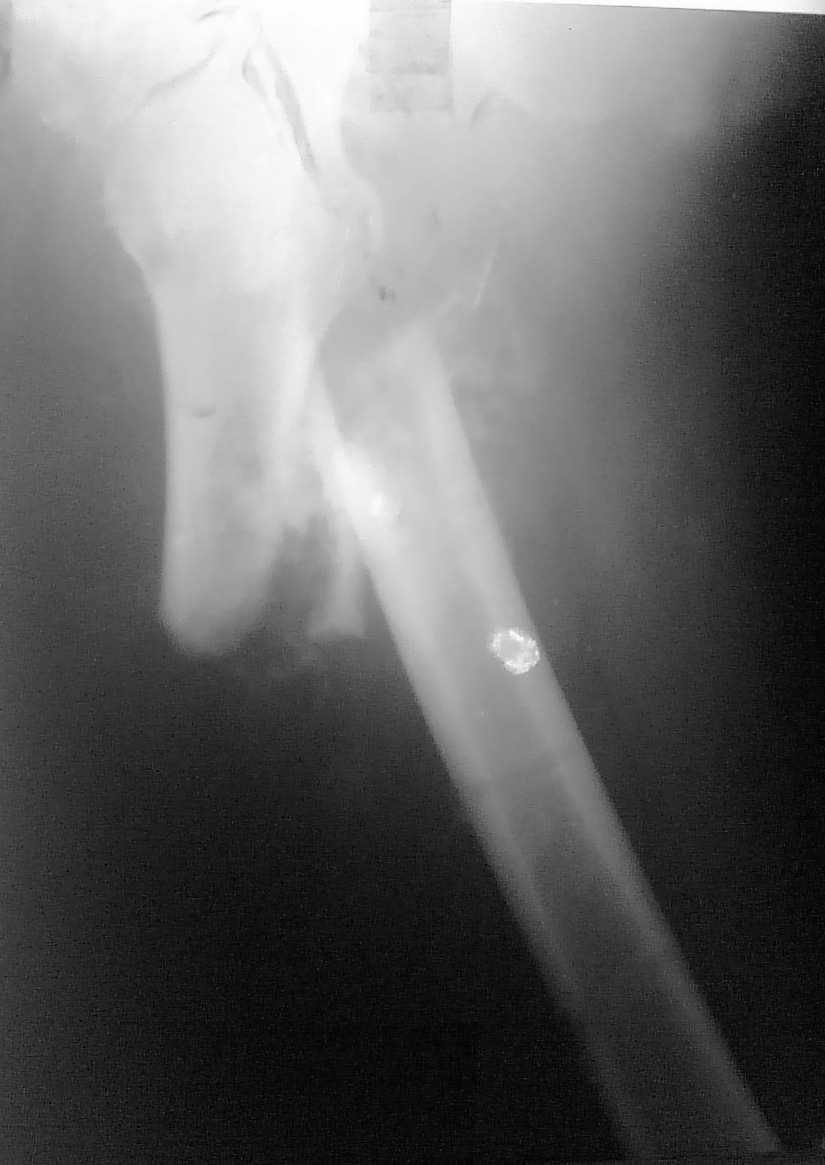

[Ortho] Консолидирующийся перелом бедренной кости

Больной Р. 28 лет поступил 14 12 09 с изолированным переломом бедренной кости в в/3 -наложена

ССВ,в течении 12 часов развилась острая смешанная форма жировой эмболии произведена

фиксация стержневым АВФ, ИТ в ОРИТ до 24 01 10, на данный момент больной в отделении

травматологии, фиксирован ССВ имеем такую рентгенологическую картину,умеренный шат в

зоне перелома ,грубые психические нарушения, лабораторные показатели нормализовались,

раны зажили. Вопросы относительно фиксации и репозиции: 1 возможен ли И-медуллярный МОС

(учитывая перенесенную тяжелую форму ЖЭ)? на данный момент отдаем предпочтение накостному